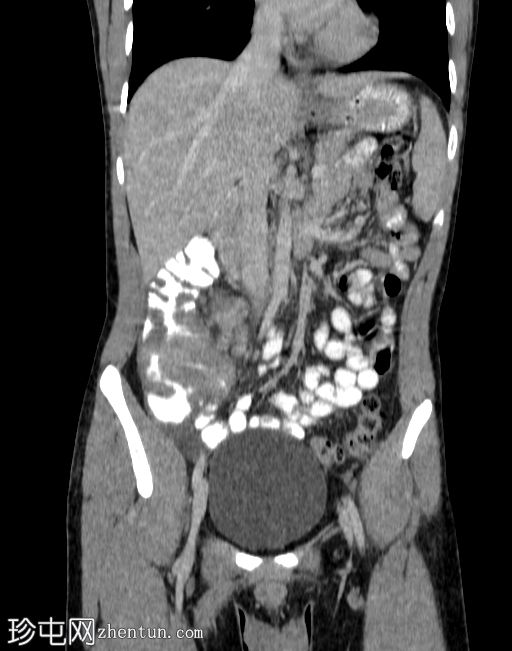

冠状位增强扫描(门静脉期)

可见盲肠和末端回肠弥漫性环周肠壁增厚,导致严重的肠腔狭窄。可见多个区域淋巴结肿大,最大者大小为2.4 x 2.2 cm,伴中央坏死。

右侧结肠旁沟可见少量游离液体和脂肪条索影,盆腔内可见少量游离液体。